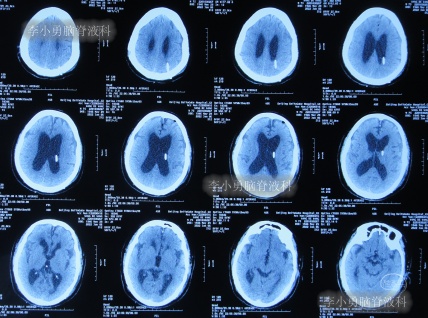

发现脑积水后8天即2020年11月6日,就诊于第2家的上海的某三甲医院,入院后再次检查(图-2)后诊断为正常压力脑积水。

图-2:2020年11月11日头部核磁